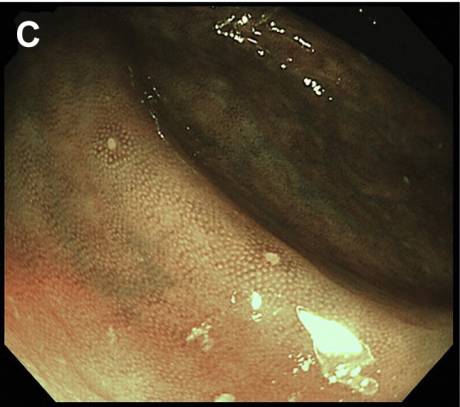

而下消化道内镜检查结果显示:白色小斑点样病灶贯穿结肠(图C,窄带成像),且直肠黏膜水肿(图D)。但是末端回肠未见明显异常。

注:内镜窄带成像术(Narrow Band Imaging,NBI),是利用滤光器过滤掉内镜光源所发出的红蓝绿光波中的宽带光谱,仅留下窄带光谱用于诊断消化道各种疾病。